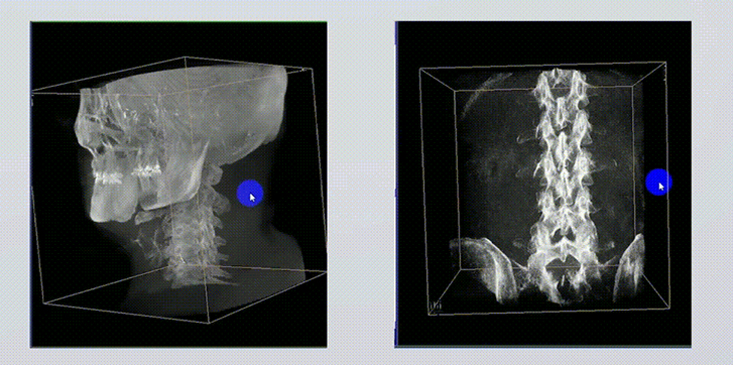

1、術(shù)中實時三維成像

術(shù)中三維成像和橫斷面圖像提供多角度的手術(shù)診斷信息,輔助醫(yī)生進行術(shù)中評估判斷,諸如骨折復位情況和內(nèi)植入螺釘?shù)某叽绾臀恢?,輔助手術(shù)更好地完成。

提供更大的術(shù)中三維成像視野,采集更多圖像信息,可一次拍全全段頸椎、全段腰椎、七節(jié)胸椎、雙側(cè)骶髂關(guān)節(jié)、股骨頭及單側(cè)盆骨。